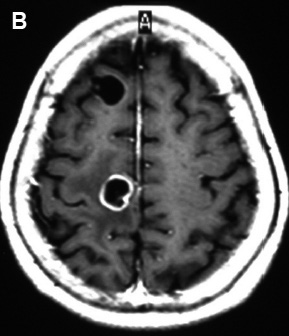

La RM facilita el diagnóstico de la neurocisticercosis ya que permite visualizar el número y la localización de los parásitos, así como su estadio evolutivo, el cual depende fundamentalmente del grado de viabilidad de los cisticercos. La RM expone mejor a los quistes intraventriculares, a los subaracnoideos, sobre todo a los de la base del cráneo, e identifica muy bien al escólex, en las secuencias T2 (22,24). Las lesiones quísticas vesiculares (quistes viables) dan señal igual al líquido cefalorraquídeo (LCR), no captan el contraste y no están rodeadas de edema. Menos frecuente pueden observarse cientos de ellos tanto en el espacio intra como en el extracraneal, denominado cisticercosis miliar (29). Cuando ocurre el fenómeno degenerativo del quiste (vesicular coloidal), da captación anular y muestra el edema periférico de grado variable (30,31). En el estadio tardío (granuloma cisticercósico), los quistes se vuelven iso o hiperintensos en RM en relación con el parénquima, y pueden captar el contraste en forma nodular o anular (quiste no viable). Las calcificaciones por lo general son pequeñas, únicas o múltiples, y raramente grandes (27,28,29). La RM muestra el compromiso de la hipertensión endocraneana dada por hidrocefalia, obstructiva por quiste intraventricular o comunicante por las leptomeninges basales o por aracnoiditis, captadoras de la sustancia paramagnética de contraste (30).

En la figura 4, se observa en la imagen axial del cerebro por RM un cisticerco vesicular coloidal frontal anterior derecho y otro frontal posterior del mismo lado, captador en anillo y rodeado de edema.